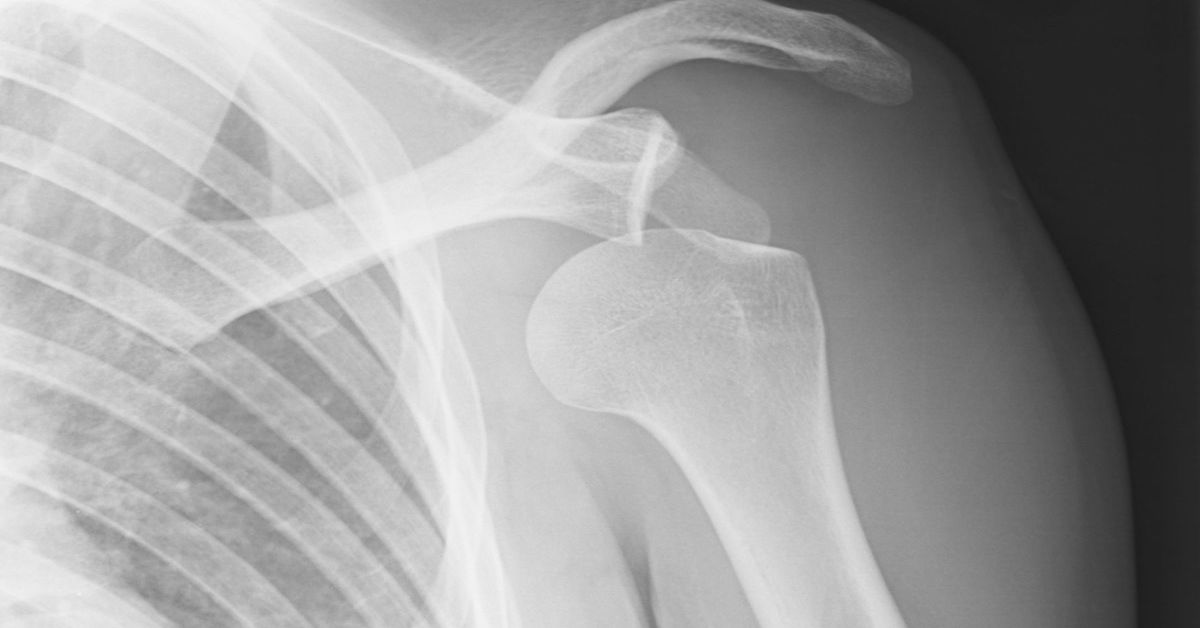

Kol kemiğinin omuz yuvasından çıkmasıdır. Omuz çıkığı, genellikle ani bir darbeyle oluşur. Omuzda şiddetli ağrı görülür. Hareket kısıtlanır. Şişlik ve şekil bozukluğu olabilir. Spor kazaları sık nedendir. Tedavi için kemik yerine oturtulur. Sonrasında fizik tedavi gerekebilir. Erken müdahale önemlidir. Tekrarlama riski vardır. Uygun egzersizle korunmak mümkündür.

Çıkık sonrası ilk müdahalede, omuz bölgesine buz uygulanması, şişliği azaltır ve ağrıyı hafifletir. Omuzun dinlendirilmesi ve aşırı hareketlerden kaçınılması önemlidir. Omuz çıkığı olan bir kişiye genellikle acil serviste doktor tarafından manuel redüksiyon yapılır. Bu, kemiklerin yerlerine geri yerleştirilmesini sağlar. Tedavide, omuz eklemi bir süre için sabit tutulur.

Kolaskop veya atel gibi ortopedik cihazlar kullanılarak hareket sınırlanır. Çıkık sonrası omuzun iyileşmesi için genellikle 2-6 hafta kadar dinlendirilmesi önerilir. Tedavinin bir parçası olarak, fizik tedavi uzmanı tarafından belirlenen egzersizler yapılabilir. Bu egzersizler, omuz kaslarını güçlendirmeyi ve eklemi tekrar hareket etmeye alıştırmayı amaçlar. Esneklik ve hareketliliği artıran terapilerle omuzun eski haline dönmesi sağlanır. Eğer çıkık sık sık tekrar ediyorsa veya manuel redüksiyonla düzeltilmesi zor oluyorsa, cerrahi müdahale gerekebilir.